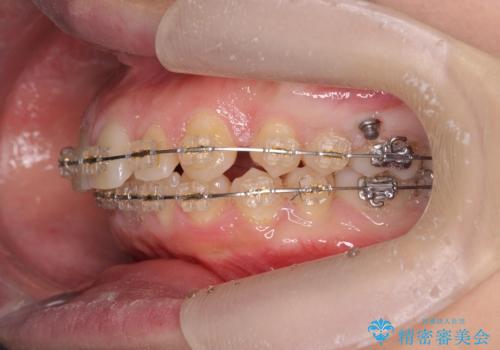

深い噛み合わせ、すきっ歯の改善 ワイヤーを用いたマルチブラケット矯正

- 矯正装置

- ワイヤー矯正

- 噛み合わせが深く、前歯が突き出て隙間が出てきたことの改善を希望され矯正治療の相談で当院に初診来院されました。

ワイヤーを用いたマルチブラケット矯正を行うことで深い噛み合わせを改善し、前歯の隙間もなくし審美的な歯列へと治療をおこなっていきます。

深い噛み合わせの改善は前歯の圧下が必要なため、治療期間が長期化することが多いです。